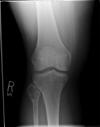

Plain Film:

Note the extension of the osteolytic lesion (arrow) towards the

diaphysis. |

- In this particular case there is

extension of the osteolytic lesion (arrow)

towards the diaphysis highly

suggestive of aggressive behavior. On the CT scan, the cortex

overlying the tumor is thickened and blurred which reflects

permeation of haversian and Volkmann's canals with subequent bone

apposition over a long period of time. This is a common feature of a

low-grade chondrosarcoma.